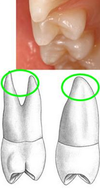

Maxillary mesial view: cusp height difference

Larger on maxillary 1st premolar

Maxillary mesial view: mesial crown concavity

Note its significance

Present on maxillary 1st premolar (good place for bacteria deposit –> cavities)

Maxillary mesial view: mesial marginal ridge groove

Present on maxillary 1st premolar

Maxillary mesial view: number of roots

Maxillary 1st premolar = 2 (buccal and pharyngeal)

Maxillary 2nd premolar = 1 root

(Important to know for root canals)

Maxillary mesial view: developmental root depression

Give the significance of this morphology

Deeper on maxillary 1st premolar (can be area for caries)